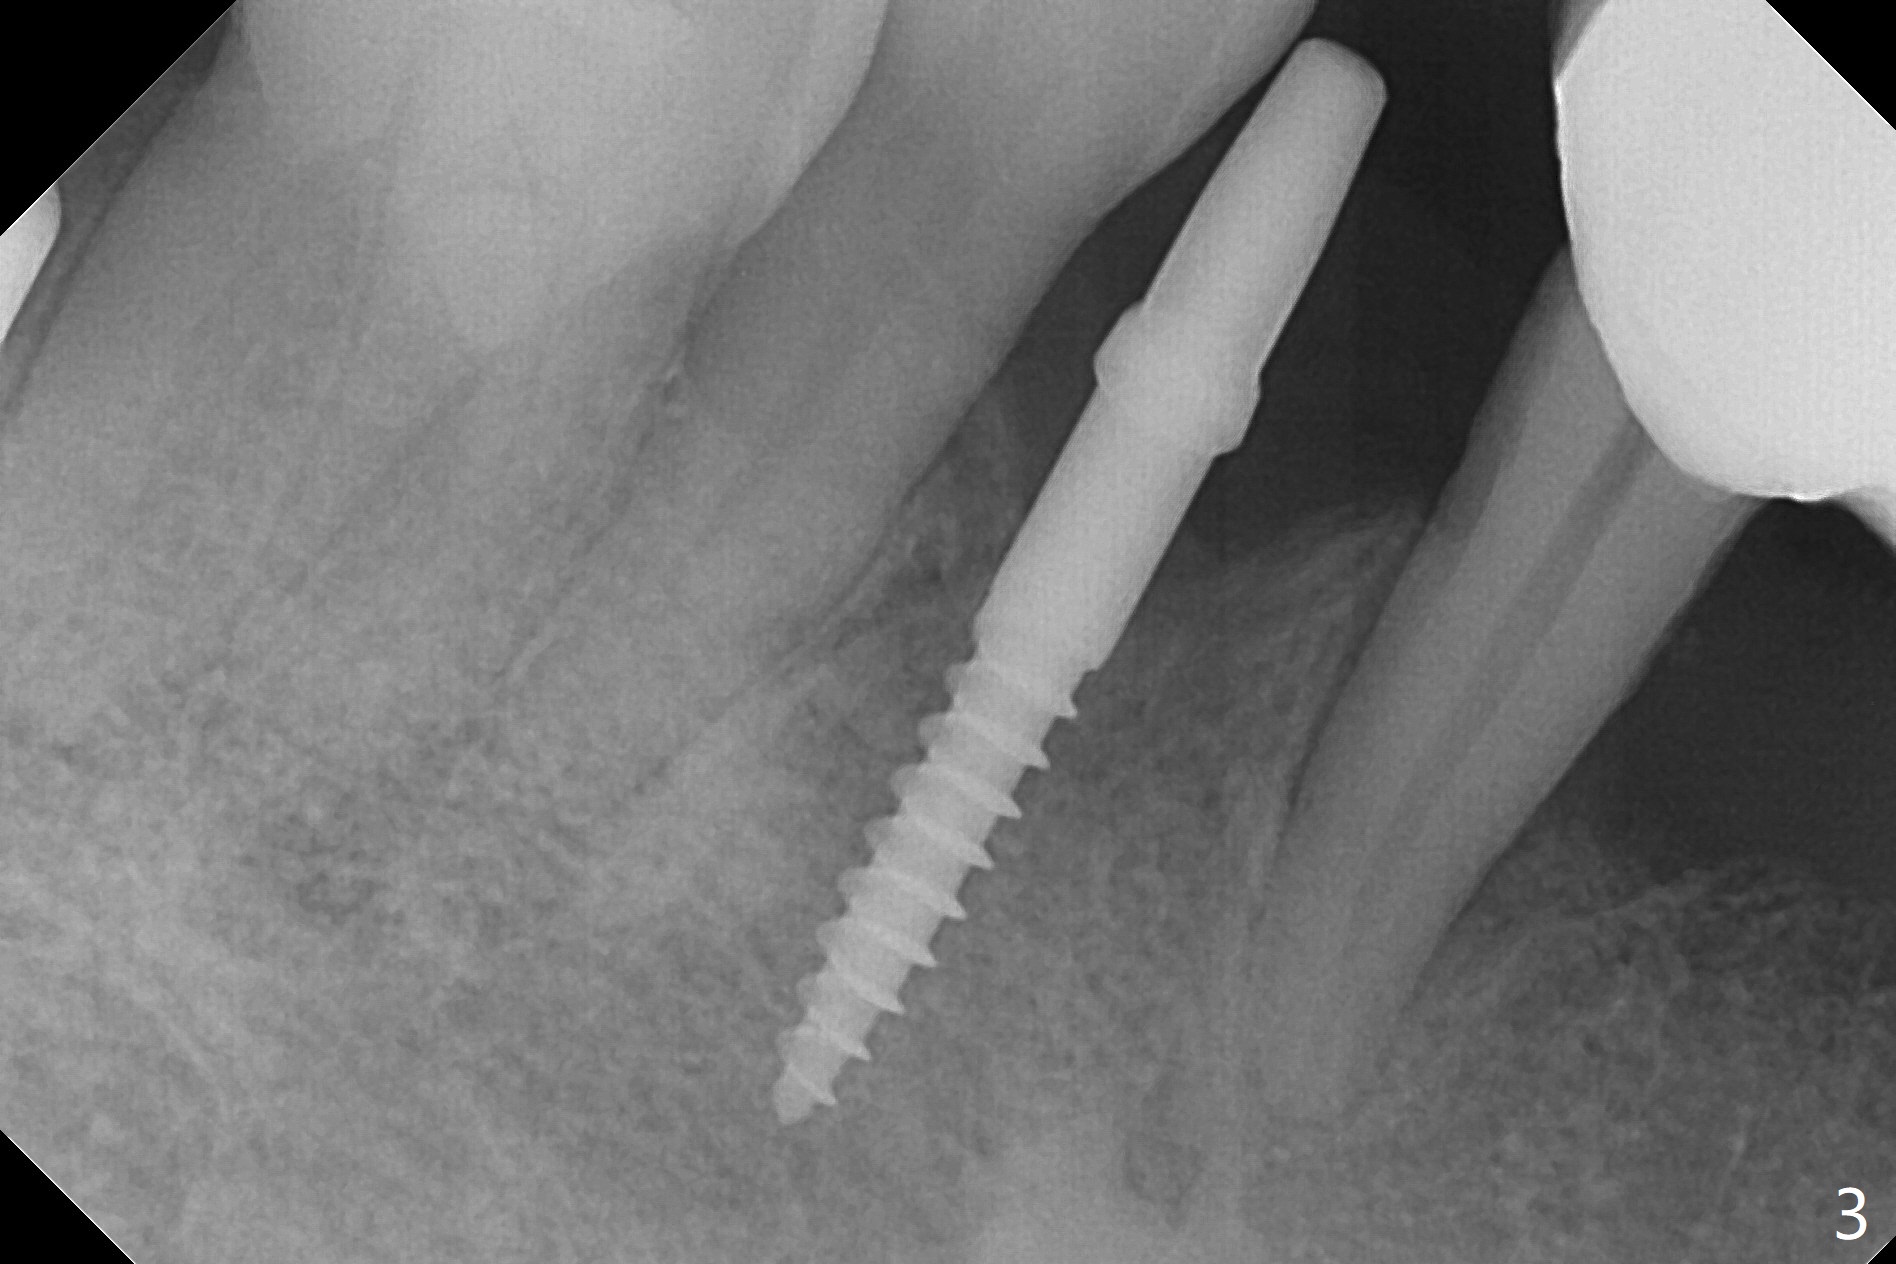

When flaps are raised at #28, the ridge appears to be narrow. Severe ridge resorption occurs 1-2 years post exfoliation. After ridge reduction, osteotomy is initiated mesially (Fig.1 (broken drill as a parallel pin)). A new osteotomy is going to be initiated as indicated by a blue line in Fig.1. It is done close to what is expected (Fig.2). When a 2.5x10(4) mm 1-piece implant is placed <20 Ncm, a major concern is where the Mental Loop is. To answer the question, intraop CBCT is taken (Fig.4). It appears that the ridge has not resorbed. If palpate more lingually (Fig.4 white <), the ridge would be found not so narrow. Preop and intraop panoramic X-ray film show sufficient bone height at the site (Fig.5,6). Low torque may be associated with low postop bone resorption, but it will take long to restore the implant.